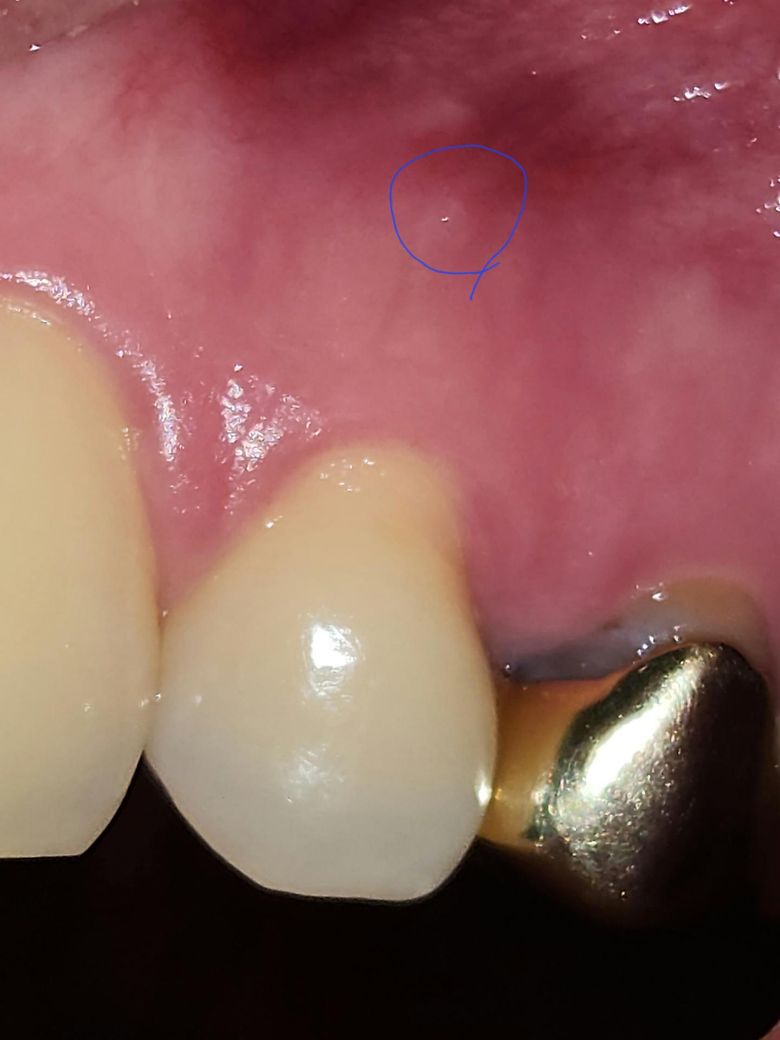

이거 동그라미 친 부분이 치주농양이고 주위에 고름같은게 있나요???

안녕하세요.. 제가 몇일전부터 혀에 해당 동그라미 사진 갖다대면 좀 볼록한듯한 느낌이 듭니다.

이거 치주농양인가요???

그리고 주위에 농양같은게 있나요????

• 1번 째 사진